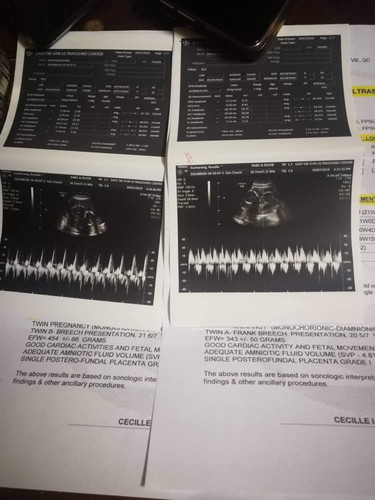

Yey!! Im 23weeks preggy na. We're getting closer and closer meeting our little twins.??❣